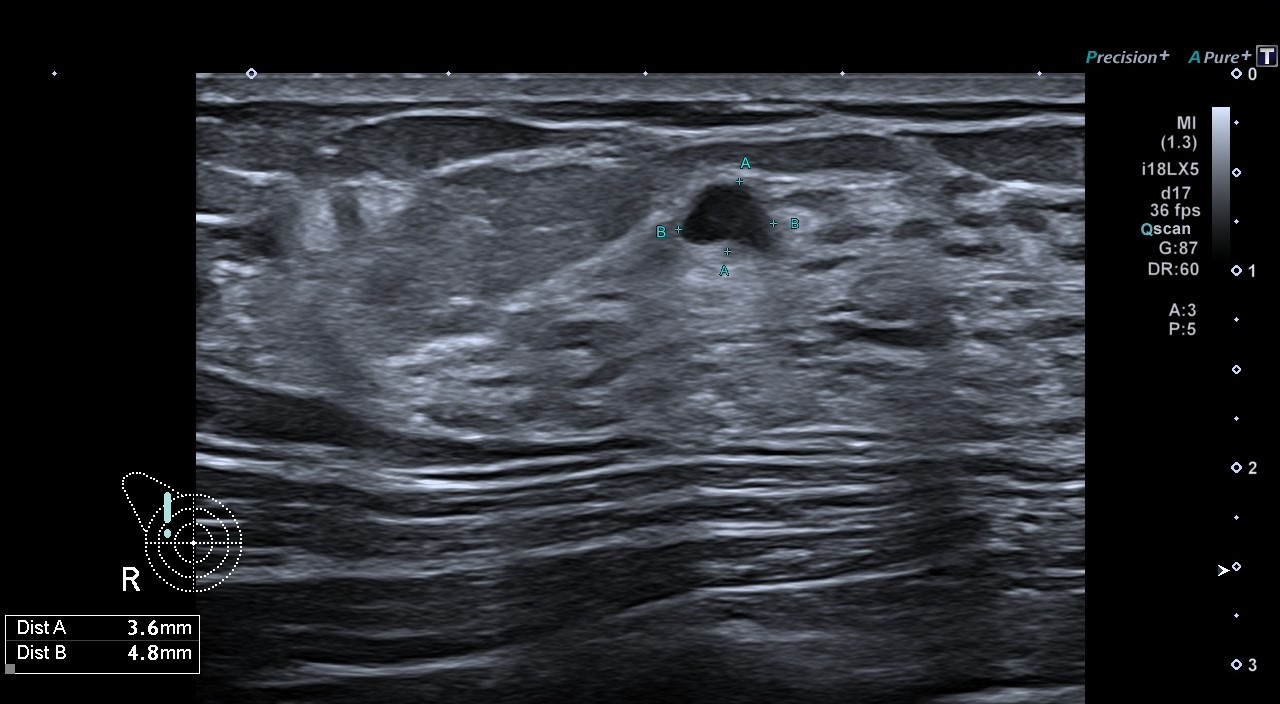

Пациентка 30л обратились в МЦ Наири с целью делать УЗИ молочной железы.

В результате исследования в правой молочной железе было обнаружено образование с неоднородной структурой размером в 5 мм, которое имело выраженное кровоснабжение.